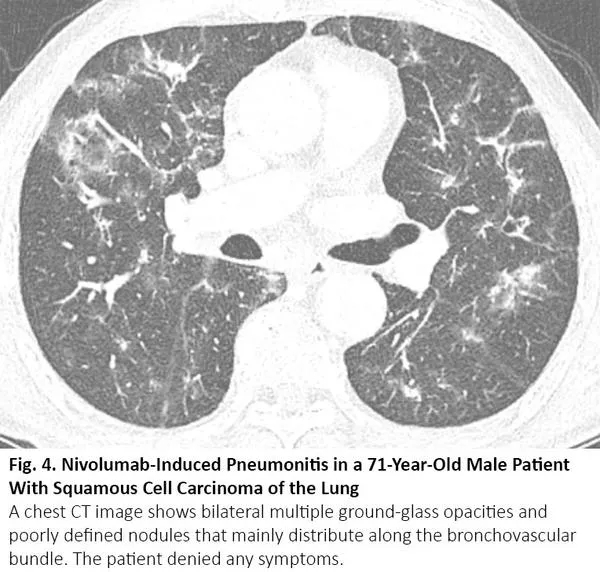

肺癌患者在病程中可能出现与COVID-19类似的CT异常,但这些异常是由于其他原因,如病毒性肺炎、癌症复发和间质性肺病。病毒性肺炎,特别是流感肺炎,在胸部CT上可表现为双侧磨玻璃样影和实性病变,胸部CT上位置分布相似10(图3),秋冬流感高发时,利用放射学检查结果来鉴别二者可能有问题。COVID-19 CT比流感肺炎CT更多见小叶间隔增厚及圆形阴影(典型肺周分布),但肺结节和树芽征相对更少。11

图3. 流感肺炎

化疗、免疫治疗可引起药物性肺炎,导致CT呈现间质性肺部疾病的影像学表现。12最常见的类型是隐源性机化肺炎,其次是非特异性间质性肺炎、超敏性肺炎和急性间质性肺炎。13其中,隐源性机化肺炎、非特异性间质性肺炎的影像学表现可与COVID-19肺炎相似(图4),反之亦然。14

图4. 一位71岁肺鳞癌男性患者出现纳武利尤单抗治疗导致的肺炎